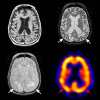

With increasing knowledge of clinical in vivo biomarkers and the pathological intricacies of Alzheimer's disease (AD), nosology is evolving. Harmonized consensus criteria that emphasize prototypic illness continue to develop to achieve diagnostic clarity for treatment decisions and clinical trials. However, it is clear that AD is clinically heterogeneous in presentation and progression, demonstrating variable topographic distributions of atrophy and hypometabolism/hypoperfusion. AD furthermore often keeps company with other conditions that may further nuance clinical expression, such as synucleinopathy exacerbating executive and visuospatial dysfunction and vascular pathologies (particularly small vessel disease that is increasingly ubiquitous with human aging) accentuating frontal-dysexecutive symptomatology. That some of these atypical clinical patterns recur may imply the existence of distinct AD variants. For example, focal temporal lobe dysfunction is associated with a pure amnestic syndrome, very slow decline, with atrophy and neurofibrillary tangles limited largely to the medial temporal region including the entorhinal cortex. Left parietal atrophy and/or hypometabolism/hypoperfusion are associated with language symptoms, younger age of onset, and faster rate of decline - a potential 'language variant' of AD. Conversely, the same pattern but predominantly affecting the right parietal lobe is associated with a similar syndrome but with visuospatial symptoms replacing impaired language function. Finally, the extremely rare frontal variant is associated with executive dysfunction out of keeping with degree of memory decline and may have prominent behavioural symptoms. Genotypic differences may underlie some of these subtypes; for example, absence of apolipoprotein E e4 is often associated with atypicality in younger onset AD. Understanding the mechanisms behind this variability merits further investigation, informed by recent advances in imaging techniques, biomarker assays, and quantitative pathological methods, in conjunction with standardized clinical, functional, neuropsychological and neurobehavioral evaluations. Such an understanding is needed to facilitate 'personalized AD medicine', and eventually allow for clinical trials targeting specific AD subtypes. Although the focus legitimately remains on prototypic illness, continuing efforts to develop disease-modifying therapies should not exclude the rarer AD subtypes and common comorbid presentations, as is currently often the case. Only by treating them as well can we address the full burden of this devastating dementia syndrome.